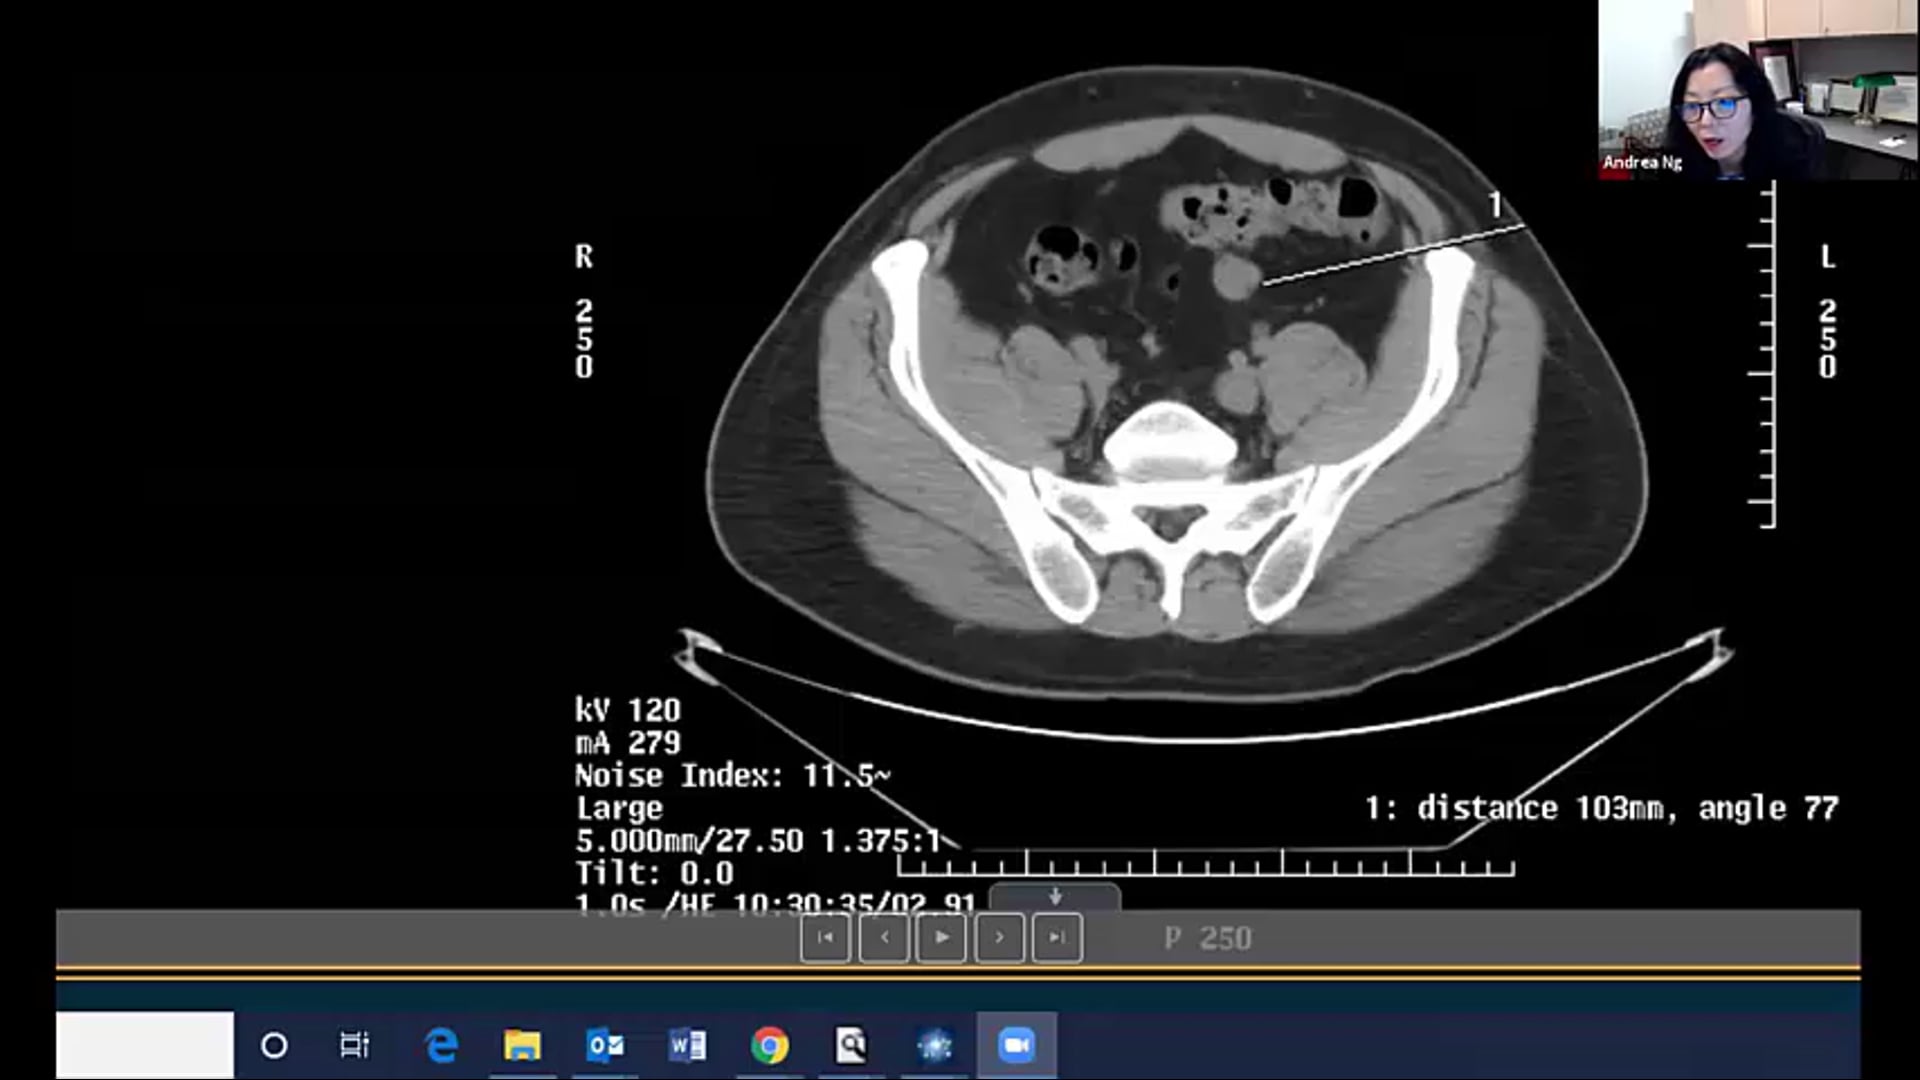

04/21/21 - Dr. Andrea Ng - Radiation Oncology - Lymphoma

05/12/21 - Dr. Andrea Ng - Radiation Oncology - Lymphoma

Lymphoma radiation, dose, local palliation, CTV